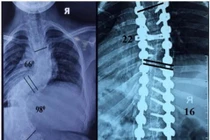

(khoahocdoisong.vn) - Lần đầu tiên Bệnh viện Đa khoa Phú Thọ đã phẫu thuật thành công chỉnh hình cột sống cho trẻ bị vẹo cột sống nặng > 45 độ. Đây là một kĩ thuật phức tạp, thường được triển khai ở bệnh viện tuyến trung ương. Phẫu thuật sớm không chỉ giúp trẻ lấy lại vóc dáng mà còn tránh các biến chứng nguy hiểm về chức năng hô hấp, tim mạch...

(khoahocdoisong.vn) - Biến dạng cột sống rất nặng và cứng nên bắt buộc phải phẫu thuật 2 đường. Phẫu thuật giúp chỉnh cong vẹo, trẻ cao thêm được 11-13cm. Hãy nhận biết các dấu hiệu trẻ bị biến dạng cột sống để cho trẻ đi khám sớm.